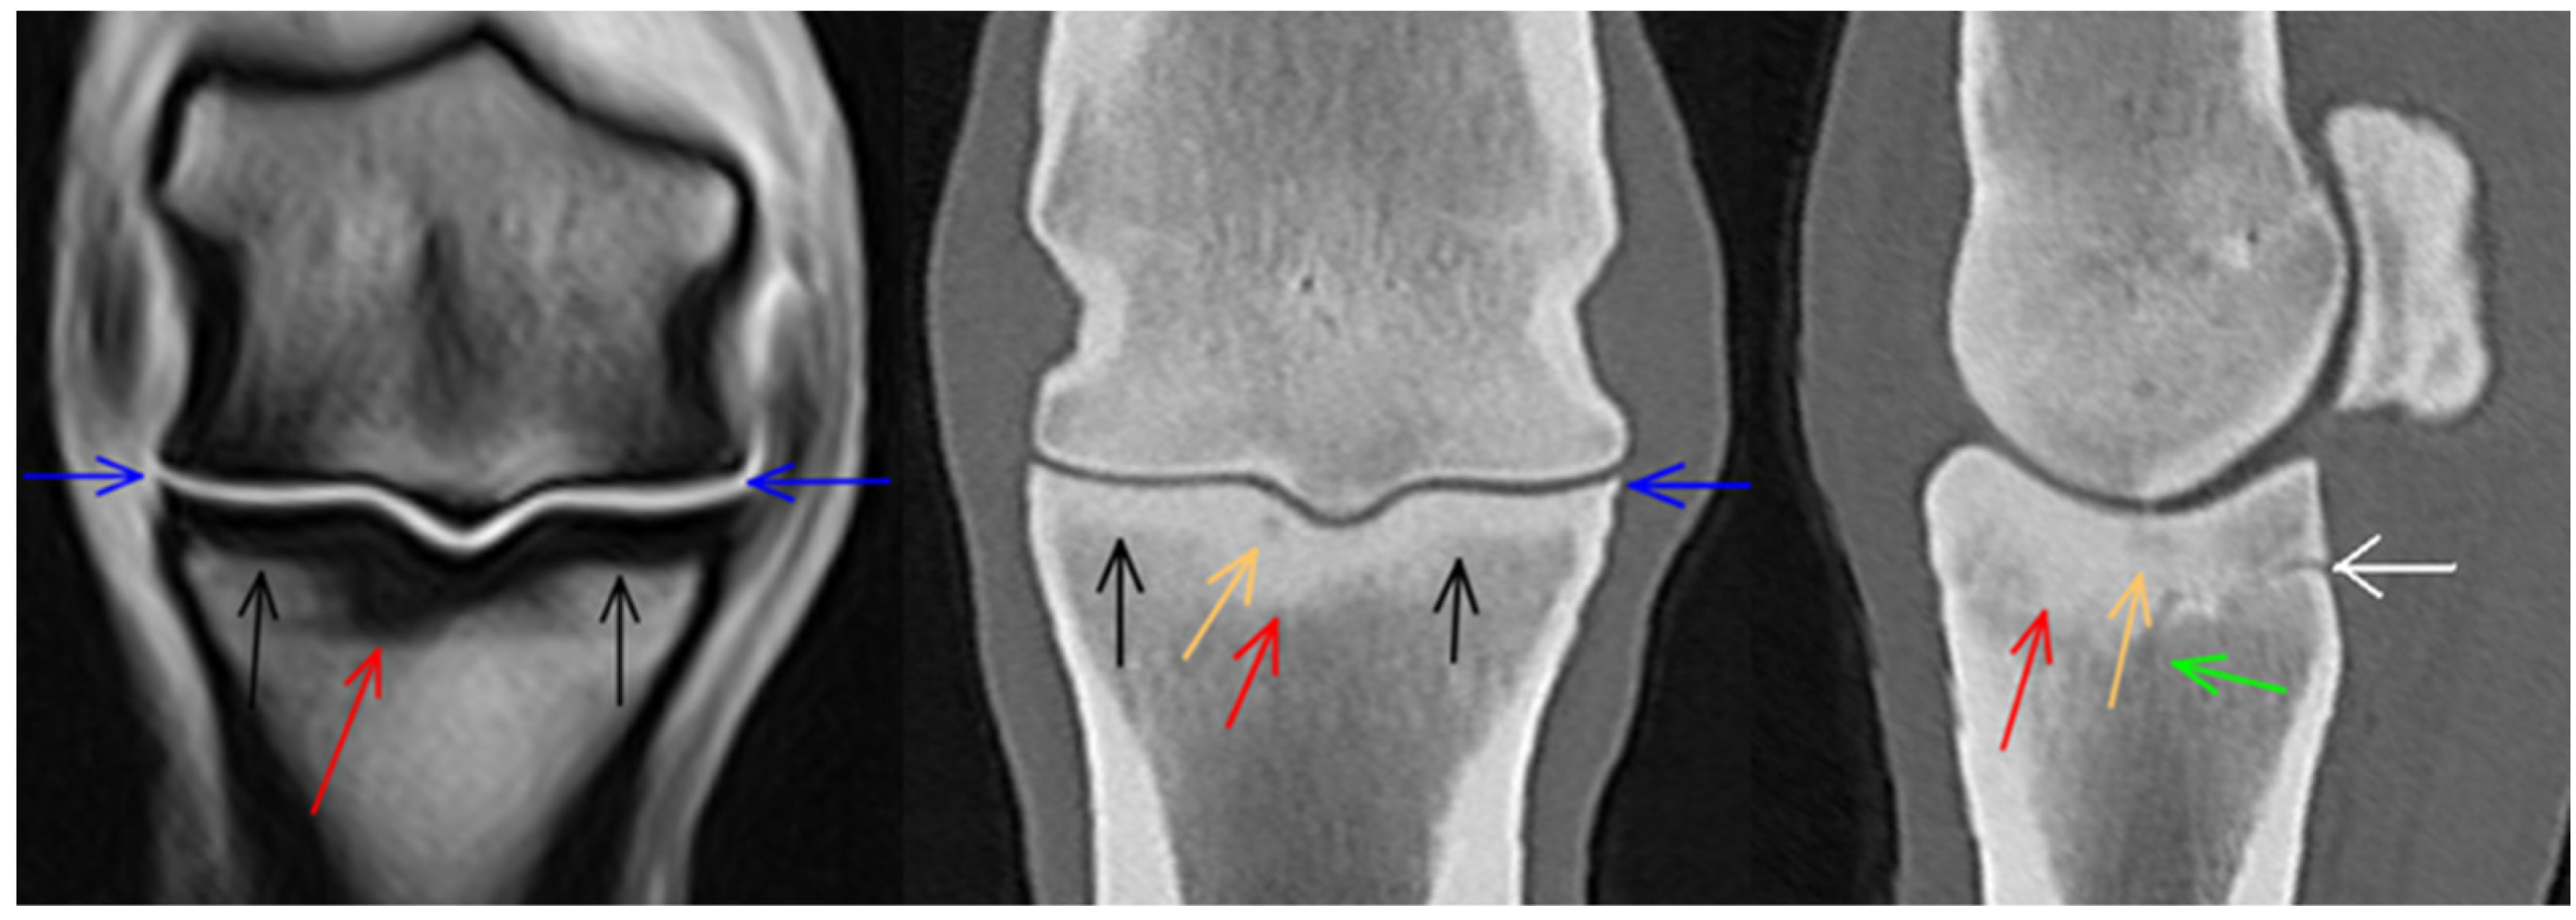

3.1. Third Metacarpal Bone

3.2. Proximal Phalanx

3.3. Proximal Sesamoid Bones

3.4. Soft Tissues